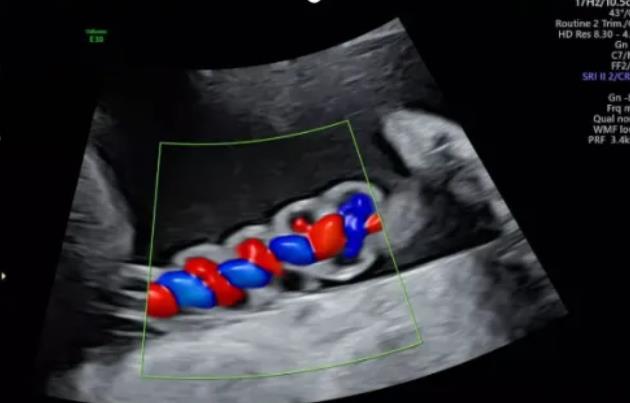

漯河市中醫(yī)院健康科普:超聲檢查之臍帶螺旋

聲像圖特征:臍動(dòng)脈表現(xiàn)為過(guò)度螺旋,臍血管變細(xì),縱切面呈“麻花狀”,橫切面呈“鼠眼狀”;

2、臍帶螺旋過(guò)松

聲像圖特征:胎兒臍帶縱切面示血管呈平行排列,螺旋稀少,彩色多普勒血流成像示臍帶血管內(nèi)充滿(mǎn)的紅藍(lán)血流呈平行排列,麻花狀螺旋消失。